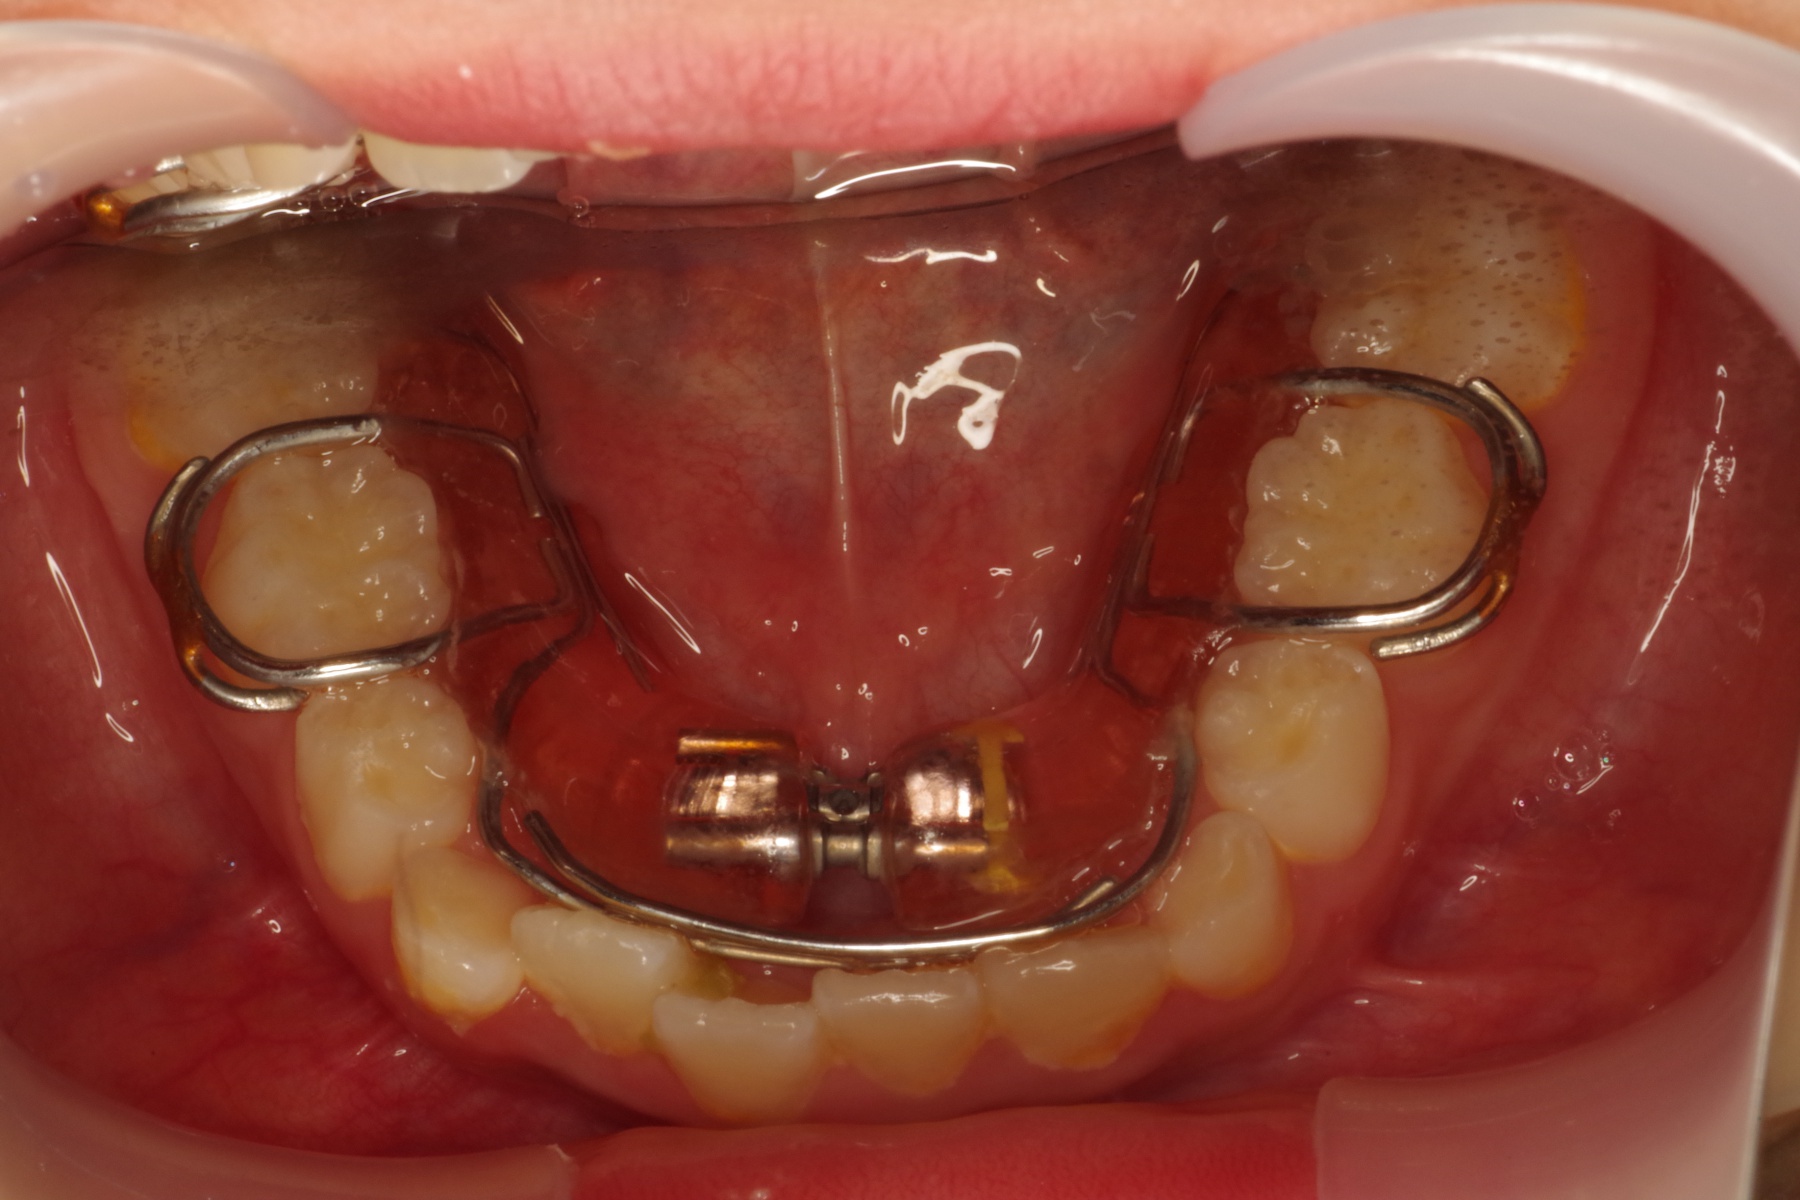

当医院ではお子様の矯正に顎の成長をサポートするような装置を使い、歯ならびを矯正します。

取り外し出来る装置のため、お子様の負担も少なく、気軽に使用できます。

当医院では歯並びだけでなく咬み合わせの確認も行っていきます。

適応年齢は小学生~中学生ですが、それ以前の年齢のお子様も定期健診で様子を診ていきますのでお気軽にご相談下さい。